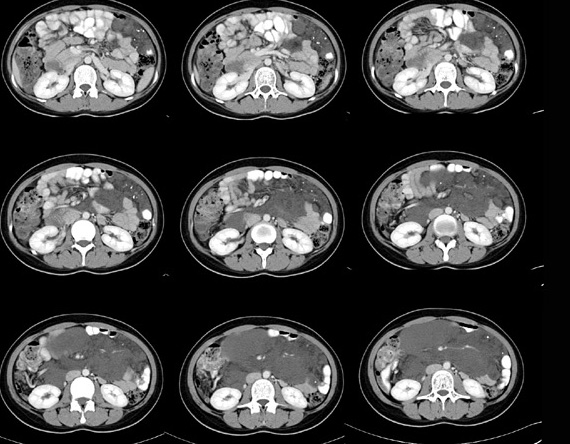

女性,28岁,停经3月,腹部膨隆1月,产前检查发现腹部占位

{肿块中心ct值27hu,增强后,动脉期、门脉期均无明显强化)

1 肠系膜肿块诸期无明显强化,肠系膜血管包绕其中但其周围仍见脂肪称“脂肪环征”;2 肠系膜血管远端较近端细,于重组像上见血管周围有强化结节为炎性结节,3肿块内见部分脂肪密度及少许点状钙化。4 腹膜后无肿大ln。

需与恶性病变鉴别,脂肪环征为重要点。亦需与卵巢源性肿瘤鉴别,年龄以及未见“卵巢静脉征”为要点。

患者手术病理:腹腔囊性淋巴管瘤,象这样充满整个腹腔的的确很少见